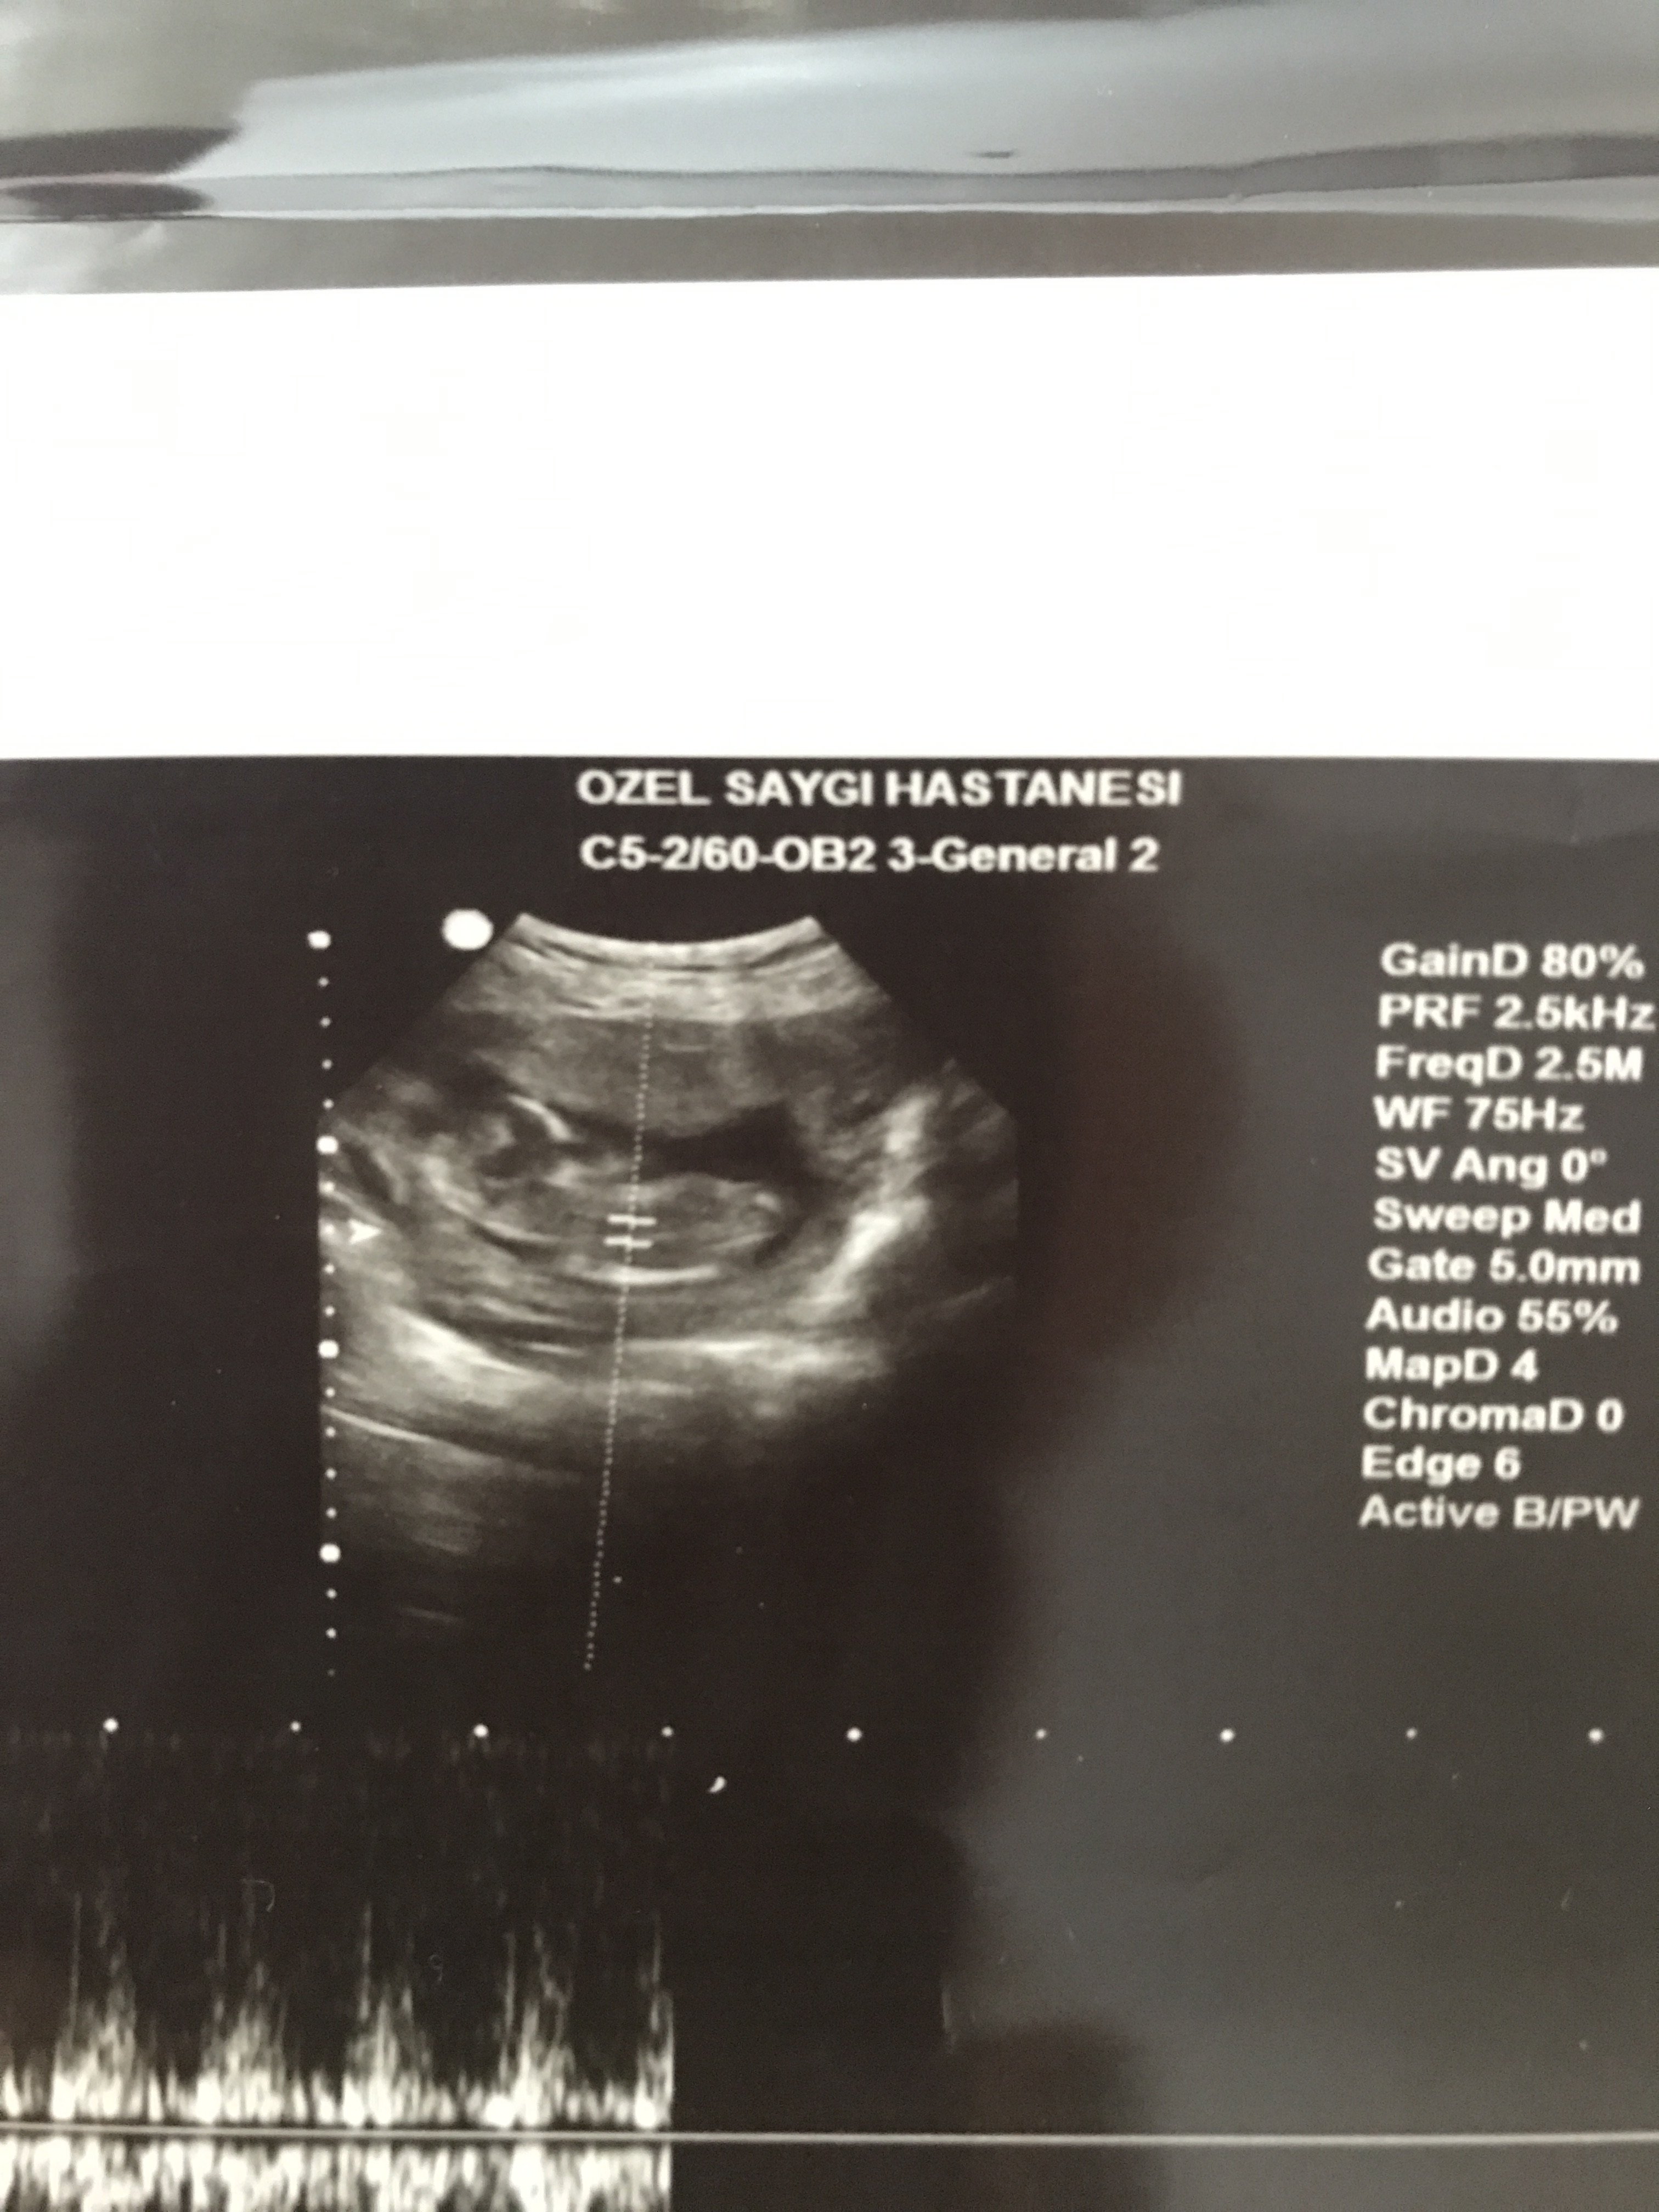

Nub teorisine göre cinsiyeti değerlendirir misiniz

Burda 13+5 nuba göre bakabilir misiniz teşekkür ediyorum resimleri ekliyorum